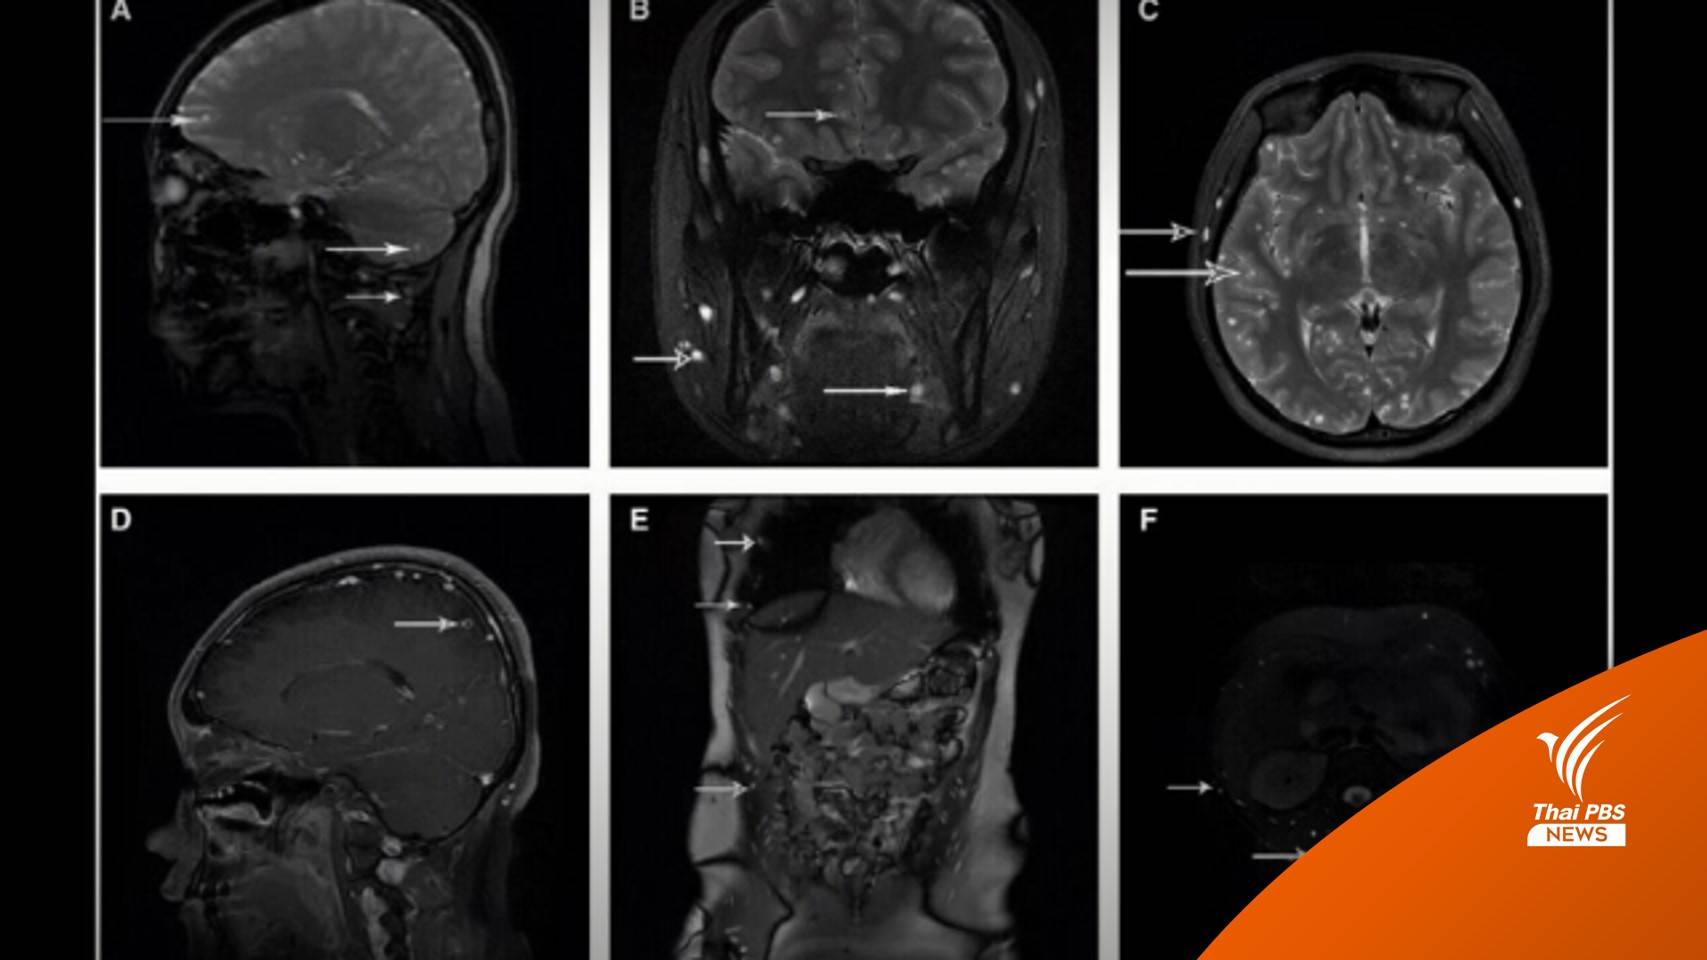

ไทยพีบีเอส สืบค้นถึงไปต้นโพสต์ พบว่าเป็นแพทย์หญิงคนหนึ่งที่ได้นำมาโพสต์เคสกรณีศึกษาผู้ป่วยที่มีอาการปวดหัวและปวดท้องเรื้อรัง 4 เดือนก่อน ผู้ป่วยเคยเข้ารับการรักษาที่โรงพยาบาล เนื่องจากปวดหัว และอาเจียน ตอนนั้นผู้ป่วยได้รับการทำ CT ที่ศีรษะและท้อง

แพทย์อ่านผลว่าปกติ ตอนนั้นแพทย์วินิจฉัยว่าเป็นไข้สมองอักเสบ และภาวะความดันในกะโหลกศีรษะสูงโดยไม่ทราบสาเหตุ แต่หลังทำการรักษากลับไม่หายจึงได้ทำ MRI จึงได้เห็นภาพดังกล่าว

เมื่อซักประวัติเพิ่มเติมจึงยอมรับว่า เคยกินไข่พยาธิเข้าไปจริง เพื่อลดน้ำหนัก โดยซื้อกินในรูปแบบแคปซูล ซึ่งเคสนี้หมอได้ให้ให้ยาฆ่าพยาธิหลายชนิด โดยให้กินครั้งแรกนาน 10 วัน แล้วขยายเป็น 20 วัน หลังผ่านไป 4 คอร์ส พบว่าพยาธิได้หายไปทั้งหมด